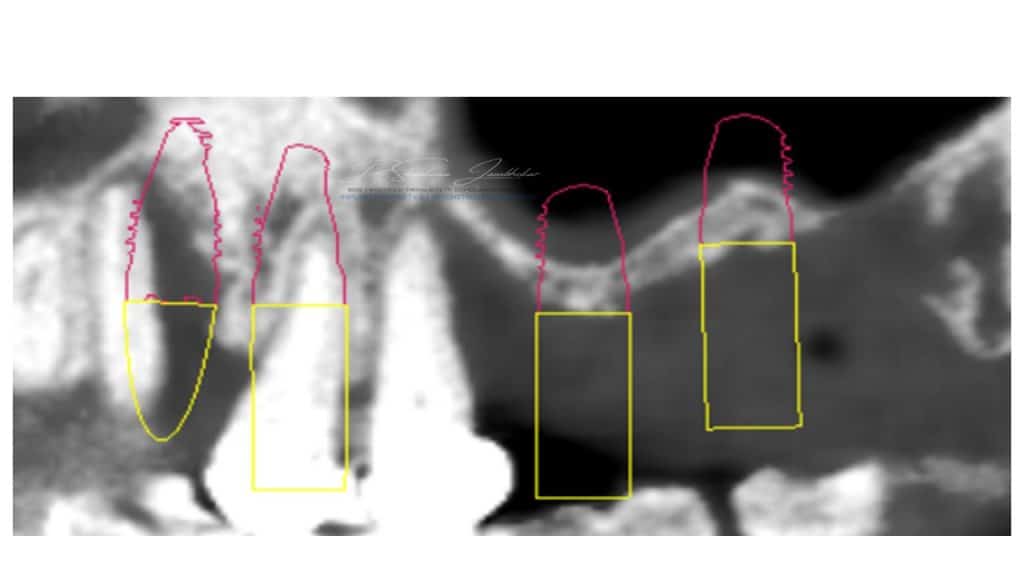

Radiographic examination revealed radiolucent lesion with 23,25 and reduced residual ridge dimensions with sites 26 & 27. Cone beam CT (CBCT) evaluation was performed for available quantity & quality of bone at the proposed implant sites using CS 3D Software.

Implant treatment Planning on CS3D software